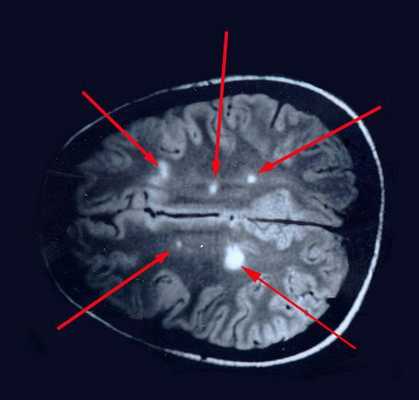

![Очаговые изменения в белом веществе мозга]()

Отдельные бляшки имеют округлую форму, они нередко сливаются и создают изменения сложных очертаний. Цвет бляшек на разрезе розовато-серый (недавно образовавшиеся очаги) или серый, желтоватый (старые очаги).

При вероятном РС, наряду с полным неврологическим осмотром, необходимо проводить исследование головного и спинного мозга при помощи МРТ. Этот способ исследования является наиболее информативным дополнительным методом диагностики. С его помощью можно обнаружить участки изменённой плотности в белом веществе головного мозга (очаги демиелинизации и глиоз). [10]

![МРТ мозга]()